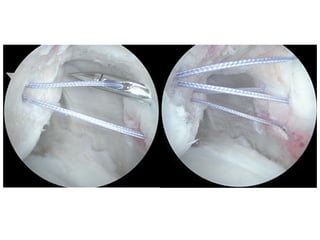

• Published by Purchase et.al

as a Technical Note in

Arthroscopy

• Posterior portal for initial

assessment

• Antero-Superior portal then

used for viewing

• Hill-Sachs and capsule

freshened

• Bankart repair prepared

Description